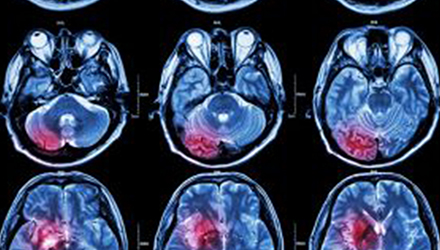

在這項研究中,研究人員使用功能核磁共振成像(fMRI)觀察大腦中血液含氧量的變化。研究人員首先研究了耳鳴患者和無耳鳴者的大腦活動,其目的是比較兩組受試者大腦處理情緒的方式。

在功能磁共振成像檢查中,受試者分別聽30種“愉悅”的聲音、30種“不愉快”的聲音和30種“中性”的聲音。這些聲音包括小孩咯咯笑,嬰兒啼哭,以及熱水壺燒開的聲音。

功能磁共振成像的結(jié)果顯示,當暴露于情緒性聲音下,耳鳴患者大腦不同區(qū)域的活動比沒有耳鳴者的活動更強烈。接著,研究人員進行了更深入的研究:耳鳴患者的大腦活躍性和耳鳴嚴重程度的關(guān)系。